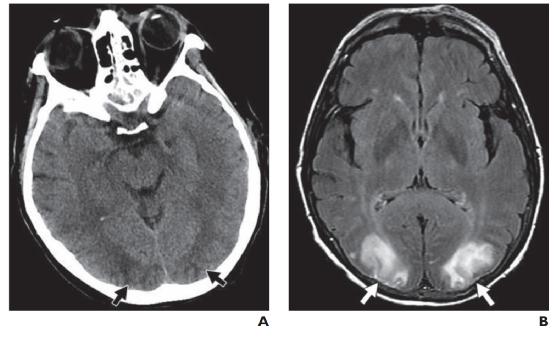

4.1创伤

脑挫伤是由直接头部外伤引起的,通常影响下额叶和前颞叶。当移动的物体撞击静止的头部时,会发生直接伤害,伤害紧挨着外伤部位。当移动的头部撞击静止的物体时,就会发生对冲伤害,从而导致力惯性传递到受影响区域的另一侧。存在细胞毒性水肿和血管源性水肿,反映出反应性细胞内代谢物积累和血脑屏障的创伤性开放。血管损伤可能导致出血(图 13A)。

剧烈的加速-减速力,例如在高速机动车事故中,可能会产生弥漫性轴索损伤。这是通过差异剪切机制发生的,并优先影响灰白质交界处、胼胝体和脑干。当在儿童和老年人身上看到时,这一系列的发现应该提示非意外创伤,特别是当病史与受伤程度不一致时。骨折、颅内出血和视网膜出血也是特征性的,并显示出空间和时间异质性。

在 CT 上,水肿或出血区域可能相当细微。MRI 更敏感,显示水肿区域在T2/FLAIR 呈高信号。微出血病灶在 GRE/磁敏感加权成像上更敏感(图 13B )). DWI 和 ADC 序列上的扩散受限表明存在缺血。带纤维束成像的 DTI 确定了白质纤维束的损伤程度。随着时间的推移,病变会发展并变得不那么明显。在晚期阶段,可能会发现残留的含铁血黄素和慢性萎缩。